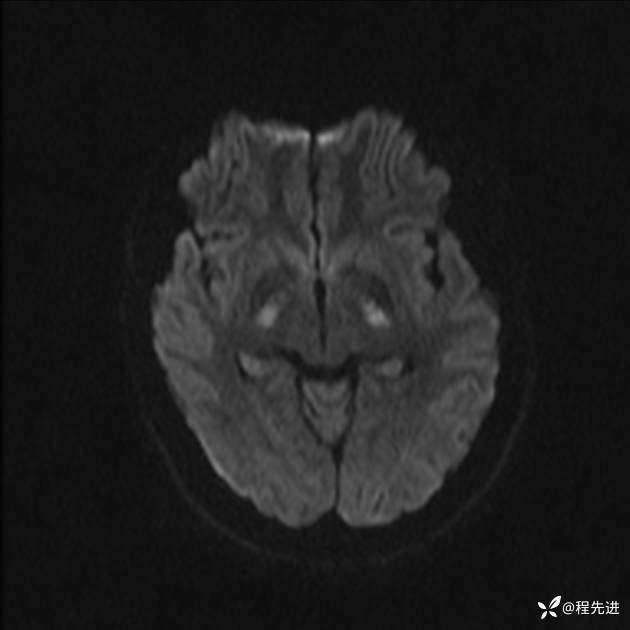

【患者信息】:女,25岁

【现病史及既往史】:言语含糊、意识状态改变1天。有下段剖宫产术10天病史。